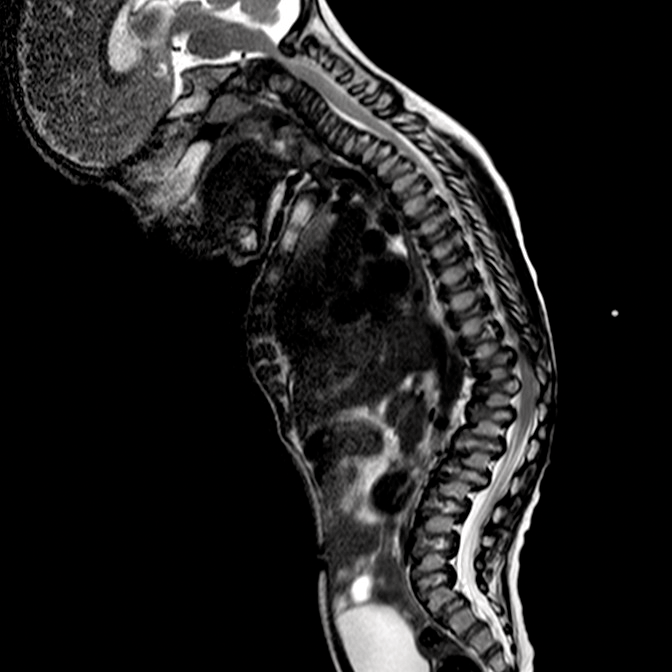

Las mucopolisacoridosis (MPS) son un grupo de enfermedades progresivas, de transmisión genética, serias, que afectan múltiples sistemas y funciones del organismo como resultado de deficiencias enzimáticas de expresión heterogénea.1-3 Las distintas manifestaciones y grados de progresión de la enfermedad —sumados a la poca frecuencia con la que aparecen en la práctica clínica — resultan en la falta de identificación de las MPS en las consultas médicas, lo que genera un diagnóstico tardío y consecuencias potencialmente devastadoras.4,5

Optimice los resultados de los pacientes a largo plazo y colabore con el inicio de un tratamiento temprano, identificando los signos de las MPS y derivando los pacientes con sospecha de la enfermedad; a un genetista o centro del metabolismo de inmediato. La consulta a un centro del metabolismo es un primer paso fundamental para el diagnóstico diferencial y un pronto inicio de tratamiento.4